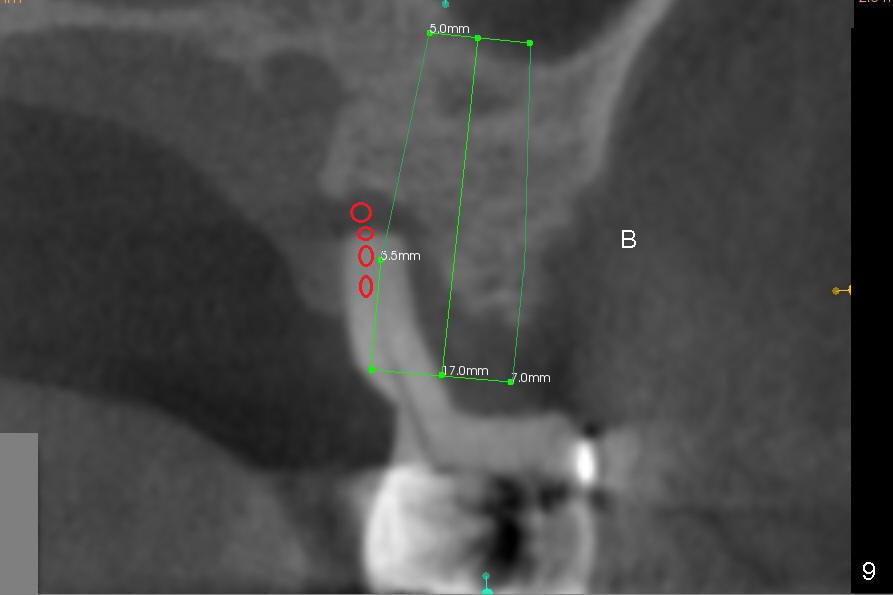

The tooth #14 is periodontally compromised with supraeruption (Fig.8-10). After immediate implant, bone graft (red circles) is needed distally (Fig.8) and palatally (Fig.9).